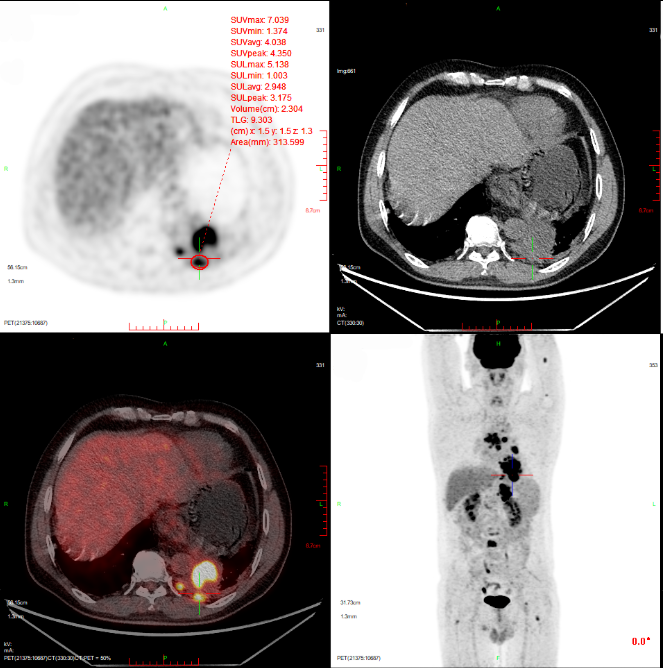

因全身疼痛不适,NRS 5分,镇痛效果不佳,于2023-03-21行PET/CT检查提示:1.左肺下叶软组织肿块6.6cm*7.3cm代谢性增高,考虑治疗后活性存在伴阻塞性肺炎;2.纵膈及左肺门、腹膜后、左侧膈脚后淋巴结转移;3.左侧胸膜转移,第5胸椎周围软组织增厚,考虑转移,后方椎管受侵;4.全身多发骨转移,脊柱退变;5.右肺上叶尖段炎性小结节。